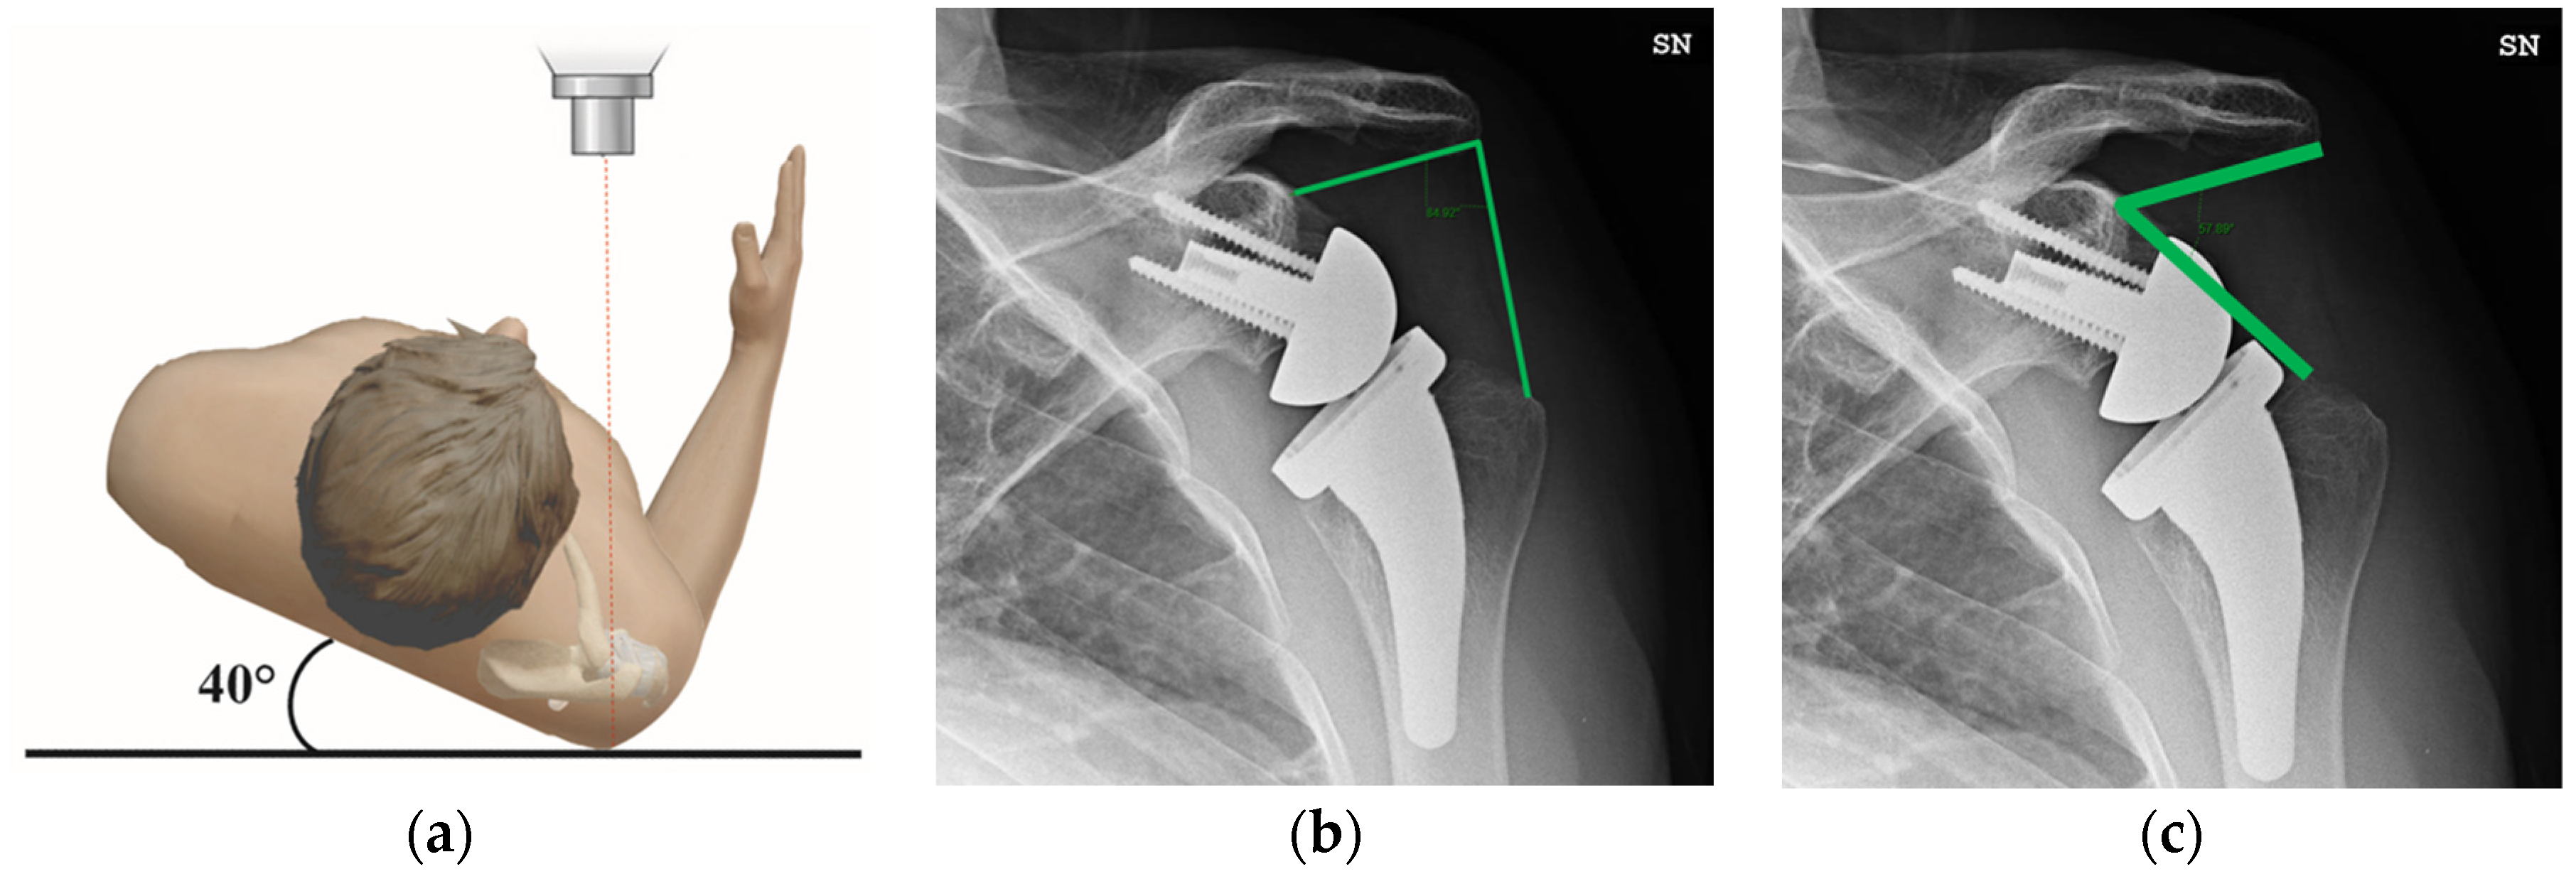

2.3. Radiographic Evaluation